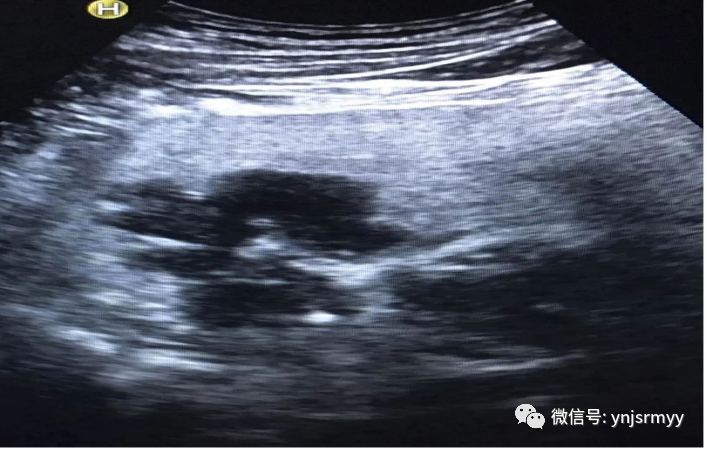

胃癌

什么是260胃镜胃肠不适,不想做胃镜,建水县人民医院胃肠超声造影检查能看!_https://www.jmylbn.com_新闻资讯_第17张